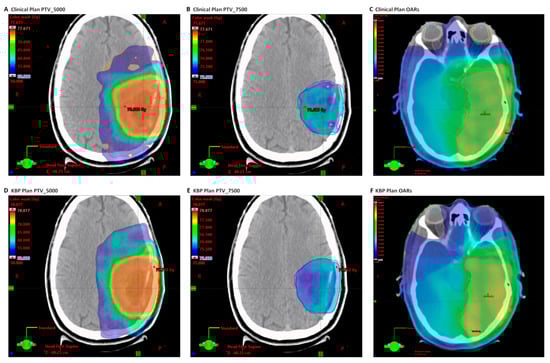

3.1. NRG-BN001 Photon Plan Quality Review

3.2. NRG-BN001 Proton Plan Quality Review